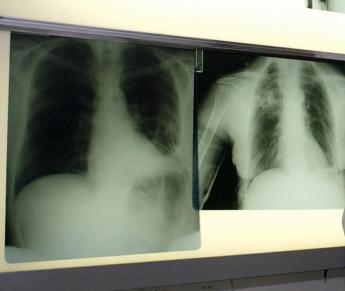

(Adnkronos) – Il timo, ghiandola chiave del sistema immunitario, protegge i polmoni dai danni del Covid a lungo termine. A svelarne l''effetto-scudo' è uno studio italiano condotto da un gruppo di ricercatori del Centro diagnostico italiano (Cdi) e dell'ospedale Fatebenefratelli dell'Asst Fbf Sacco di Milano, pubblicato su 'Applied Sciences'. Il timo – spiegano dal Cdi – è una ghiandola situata nel torace in sede retrosternale, che svolge una funzione fondamentale nella maturazione dei linfociti T del sistema immunitario. Dopo la pubertà normalmente le sue dimensioni e la sua attività si riducono e il timo viene progressivamente sostituito da tessuto adiposo, una trasformazione più evidente nel sesso femminile. Questa riduzione dimensionale rende il timo meno distinguibile nelle immagini di tomografia computerizzata (Tc). Il timo, tuttavia, può ingrossarsi nuovamente e riattivarsi in risposta a malattie autoimmuni o a un'infezione virale come quella da Sars-CoV-2, per aumentare la produzione di linfociti T e potenziare le difese immunitarie. Ricerche precedenti avevano già indicato che il timo riattivato o ingrossato è associato a una prognosi migliore nelle fasi acute della malattia da Sars-CoV-2, ma il nuovo lavoro suggerisce "un ruolo protettivo della ghiandola anche su più lungo periodo e apre a nuove prospettive di ricerca sulla sua funzione nel contrasto delle infezioni virali". Gli scienziati hanno osservato che "un timo ben visibile nelle immagini di tomografia computerizzata raccolte dopo 3 mesi dalle dimissioni ospedaliere per Covid-19 si accompagna a un migliore stato di salute dei polmoni dei pazienti in precedenza ricoverati. In particolare, nei soggetti che all'indagine radiologica mostravano un timo non ancora sostituto da grasso si osservavano zero o lievi alterazioni del tessuto polmonare. Viceversa, i soggetti in cui il timo era progressivamente sostituito da grasso, e pertanto sempre meno distinguibile nelle immagini radiologiche, mostravano alterazioni da moderate a gravi del tessuto polmonare". "Questo lavoro di ricerca – racconta Deborah Fazzini, direttore Up Imaging diagnostico e radiochirurgia stereotassica, Cdi – è nato da un'intuizione avuta durante l'osservazione radiologica: ho notato frequenti e insolite attivazioni del timo in questo tipo di pazienti, specie nelle donne, in cui la ghiandola è generalmente meno visibile. Dove il timo era evidente erano presenti meno sequele polmonari dopo l'infezione da Covid-19". "Per validare questa ipotesi – riferisce la specialista – abbiamo analizzato l'aspetto del timo attraverso la Tc del torace in 102 pazienti adulti precedentemente ospedalizzati per Covid-19, seguiti con una Tc di controllo a 3 mesi dalla dimissione. I risultati ottenuti supportano l'ipotesi che la riattivazione del timo svolga un ruolo protettivo importante, offrendo nuove prospettive sulla dinamica immunitaria legata al coronavirus e indicando il timo come un fattore chiave nella resilienza alle complicazioni polmonari post-infezione". —salutewebinfo@adnkronos.com (Web Info)